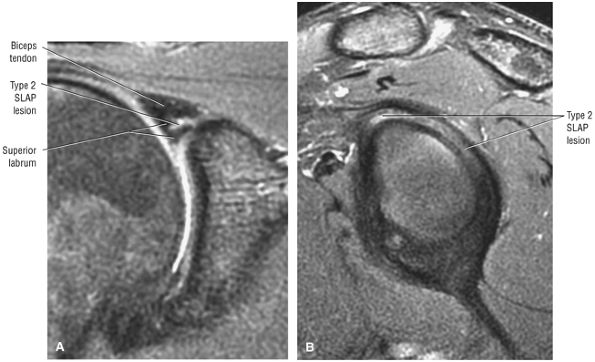

Type 2 SLAP tear extending primarily into the posterior superior labrum